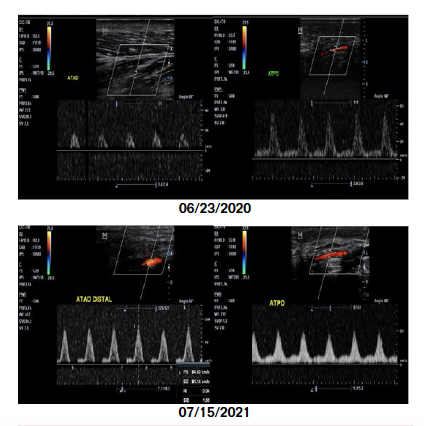

Urinary lead excretion increased an average of 3155% and cadmium 918% after the first infusion (Figure 2). No patient underwent surgery for minor or major amputations during the infusion phase, with 1 patient undergoing lower extremity endovascular revascularization. Compared to baseline, post edetate disodium urinary lead excretion decreased by 36% (P=.0004). Arterial duplex ultrasound comparisons before and after infusions with edetate disodium revealed an improvement in arterial flow after 40 infusions (Figure 3). No serious side effects related to therapy were reported. No major cardiovascular endpoints were encountered. All patients have remained free of surgical amputation since completing treatment with a median follow-up of 490 days. One patient in Argentina had a spontaneous amputation of a mummified toe, which had been present prior to the onset of therapy.

There are various study limitations. This is a small retrospective study of 9 patients; thus, any findings are hypothesis-generating and should not be brought to the clinical arena without careful thought. Larger studies with edetate disodium in high-risk patients, such as in TACT2 in patients with diabetes and myocardial infarction, and TACT3a in patients with diabetes and CLTI, will further explore potential benefits of edetate disodium. Although all patients at Mount Sinai and Rosario, Argentina received edetate disodium-based infusions, the overall infusion ingredients were not the same in the 2 countries. Finally, there was no systematic assessment of blood flow. The 2 patients in Rosario had improvements in blood flow as measured by arterial duplex ultrasound, but such clinical data are at best only suggestive.